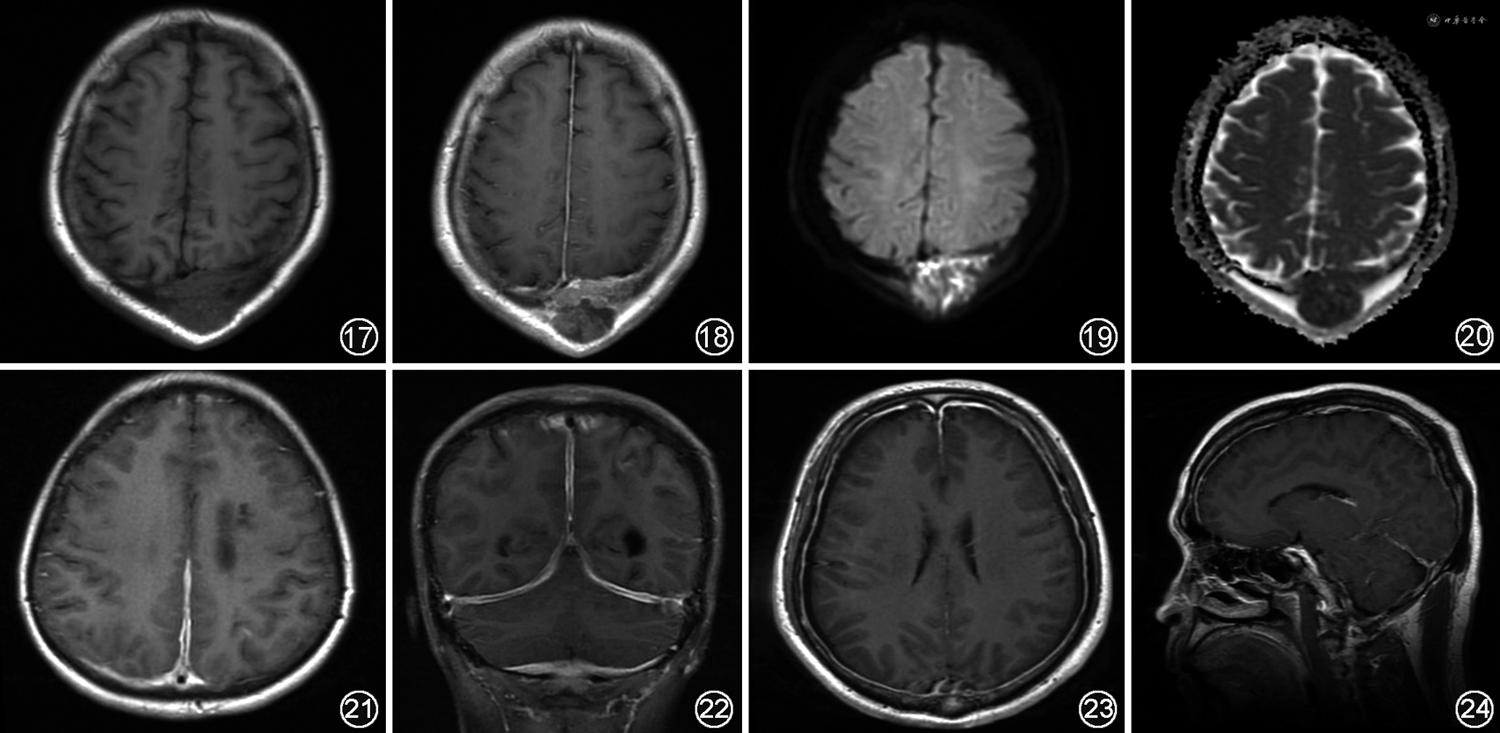

4.硬脑膜转移瘤:根据脑膜解剖分层,肿瘤的脑膜转移可分为硬脑膜转移及柔脑膜转移,多见于实体瘤及血液系统肿瘤患者[24, 25, 26]。其中硬脑膜转移是指硬脑膜被肿瘤细胞浸润,约61%为颅骨直接延伸,包括硬膜外转移及硬膜下转移[22],伴有颅骨骨质破坏。发生硬脑膜转移的非中枢神经系统性肿瘤主要有乳腺癌、前列腺癌、肺癌及恶性黑色素瘤等[27]。MRI平扫中硬脑膜病变信号可与原发肿瘤相似[28],增厚的硬脑膜在T1WI上常表现为等或低信号,但在T2WI上表现不一,可为高信号或低信号(图17~20);增强后表现为颅骨内板连续、增粗的弧形强化,且不深入脑沟及脑池,约50%的病例中存在硬膜尾征,当肿瘤细胞聚集时可形成大小不等的异常强化结节。硬脑膜转移瘤特点多样而不易鉴别,需结合原发肿瘤影像学特征综合判断。在PWI中,大多数硬脑膜转移瘤的rCBF减低,但某些转移瘤如肾癌、黑色素瘤等肿瘤因血供丰富表现为灌注明显增加。此外,某些肿瘤特征性信号也有一定提示作用,如黑色素瘤中的黑色素为顺磁性,在MRI上表现为特征性的T1WI高信号、T2WI低信号[29]。

1.肥厚性硬脑膜炎:几乎所有系统性自身免疫性疾病都可累及中枢神经系统,其中部分表现为累及硬脑膜,最常见的是肥厚性硬脑膜炎。按病因来源肥厚性硬脑膜炎可分为特发性及继发性,特发性肥厚性硬脑膜炎是指病因并不十分明确者,而继发性肥厚性硬脑膜炎中自身免疫性因素最为常见,常见于IgG4相关疾病及抗中性粒细胞胞浆抗体(anti-neutrophil cytoplasmic antibody,ANCA)相关血管炎。肥厚性硬脑膜炎是一种以硬脑膜增厚及纤维化为主要特征的罕见神经系统疾病,主要临床症状为头痛,可伴有多组颅神经麻痹[30, 31]。硬脑膜炎可通过硬膜活检确诊,或脑脊液检查作排除性诊断。在临床中硬脑膜炎症状加重快,因此无创、方便的MRI检查在诊断硬脑膜炎中有很高的价值。一般来说,硬脑膜可表现为弥漫性或局灶性增厚。增厚的硬脑膜在T1WI呈等或略低信号,在T2WI、FLAIR及DWI上呈低信号,其中T2WI信号程度与纤维成分含量有关,纤维成分越多,T2WI信号越低,增强后表现为线状或结节状强化[32];在冠状面上可见特征性的“埃菲尔夜间征”(或“奔驰征”),即大脑镰后部和小脑幕硬脑膜外周边缘强化而中央无强化[33, 34, 35](图21,22)。

低颅压综合征是一种由于颅内脑脊液量减少、压力下降,继而发生硬脑膜血管充血和间质水肿的疾病。93.1%的病例表现为体位性头痛,即卧位变换立位时头痛加重,恢复卧位时头痛消失或缓解[1]。表现为双侧硬脑膜对称、均匀增厚,可伴硬膜下积液,增厚的硬脑膜在T1WI呈稍低或等信号,T2WI呈稍高或高信号。增强后表现为弥漫性、均匀线样强化,可同时累幕上及幕下[39](图23,24)。若发生脑脊液漏,磁共振脊髓造影可观察到蛛网膜下腔异常走行的片絮状高信号。低颅压综合征还可合并获得性小脑扁桃体下疝畸形、垂体肿大、视交叉下移、脑桥变平与脑脊液池消失等其他颅内改变[40],为进一步鉴别诊断提供依据。